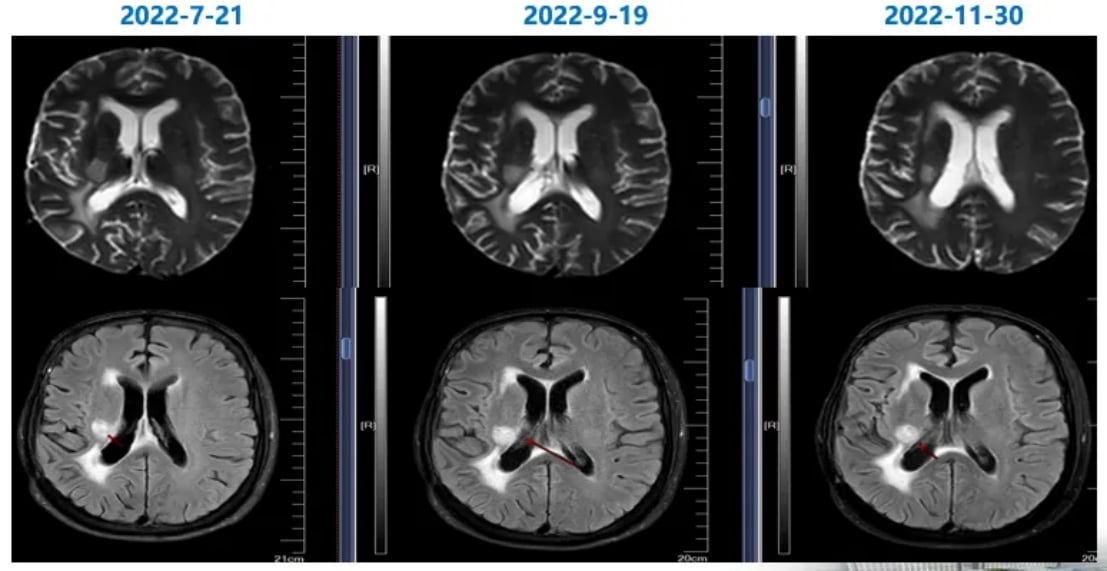

随访MRI显示,经过联合治疗后,患者脑内病灶的强化程度明显减低,部分病灶甚至消失,病情得到了有效控制。这一积极结果表明,替尼泊苷联合贝伐珠单抗方案在治疗复发性胶质母细胞瘤方面具有显著疗效。

图5 联合治疗期间,病灶强化程度逐渐减低